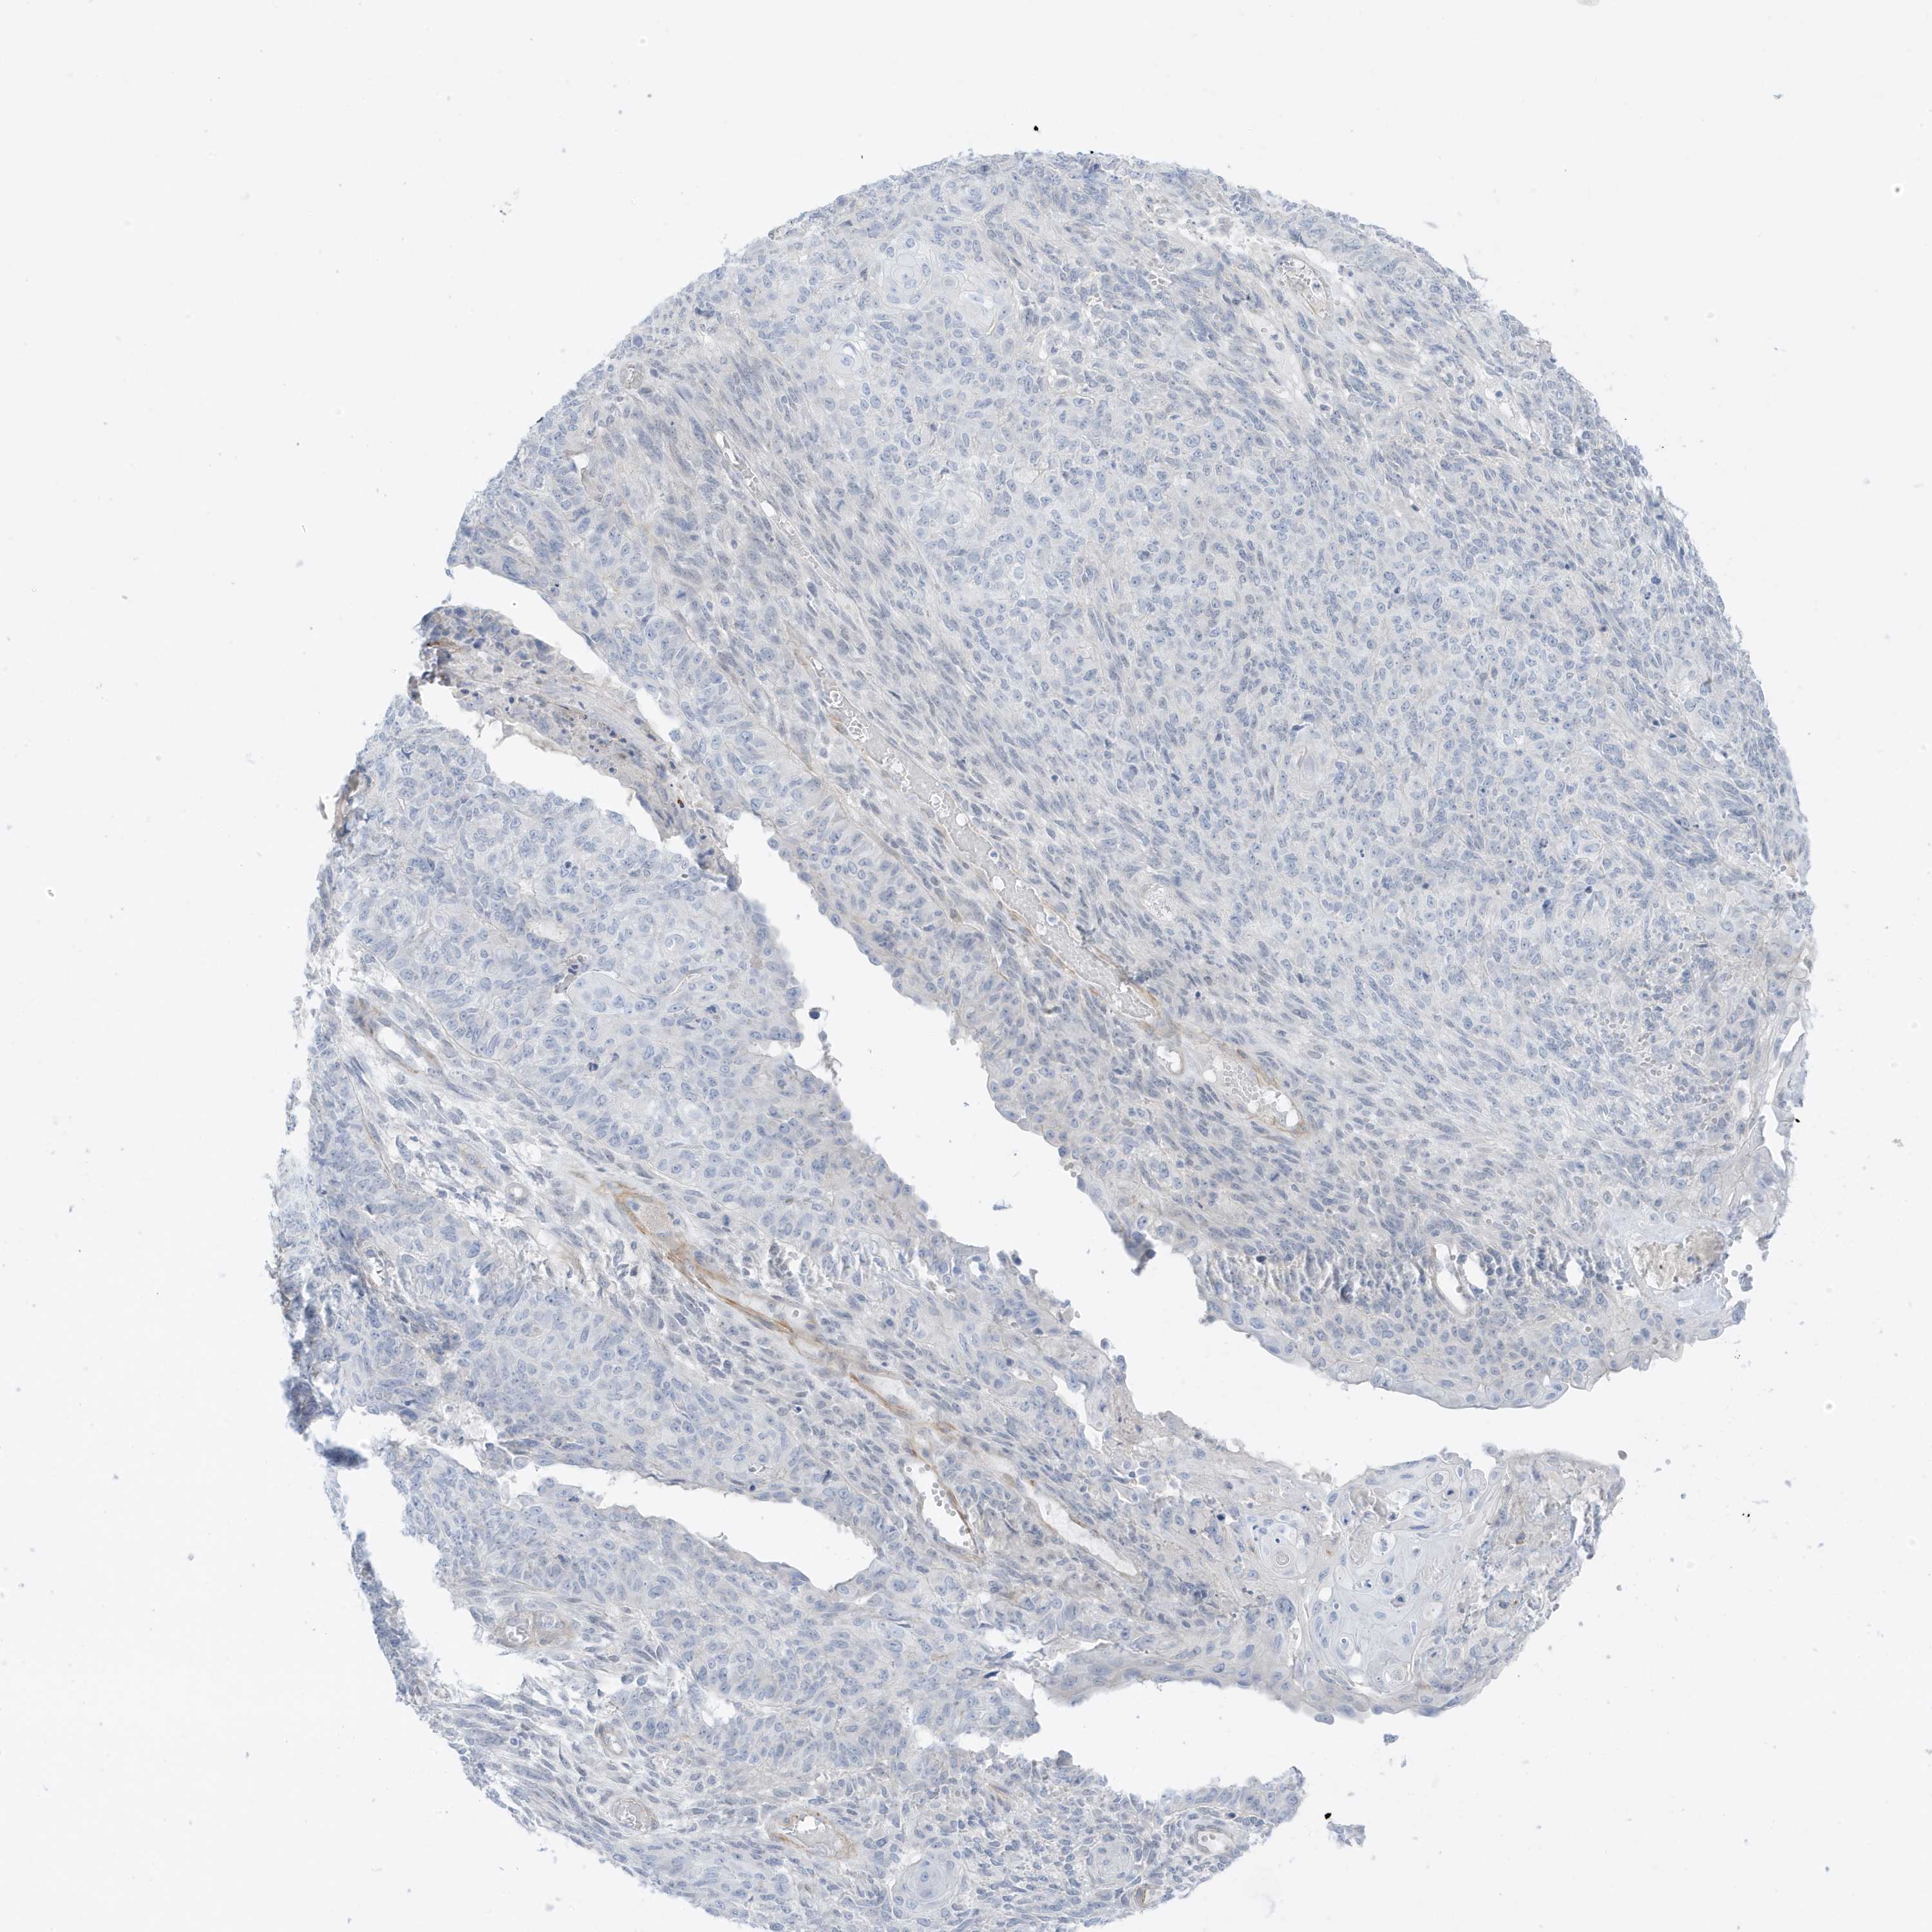

ENDOMETRIAL CANCER - Protein expressioni

A mouse-over function shows sample information and annotation data. Click on an image to view it in a full screen mode. Samples can be filtered based on level of antibody staining by selecting one or several of the following categories: high, medium, low and not detected. The assay and annotation is described here.

Note that samples used for immunohistochemistry by the Human Protein Atlas do not correspond to samples in the TCGA dataset.

Antibody stainingi

Antibody staining in the annotated cell types in the current human tissue is reported as not detected, low, medium, or high, based on conventional immunohistochemistry profiling in selected tissues. This score is based on the combination of the staining intensity and fraction of stained cells.

Each image is clickable and will lead to virtual microscopy that enables deeper exploration of all samples and also displays staining intensity scores, fraction scores and subcellular localization as well as patient and tissue information for each sample.

Antibody HPA035603

Antibody HPA035962

Staining

High

Medium

Low

Not detected

Intensity

Strong

Moderate

Weak

Negative

Quantity

>75%

75%-25%

<25%

None

Location

Nuclear

Cytoplasmic/membranous

Cytoplasmic/membranous,nuclear

Adenocarcinoma, NOS

Adenocarcinoma, metastatic, NOS